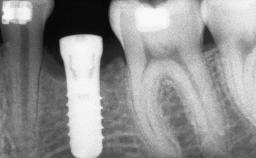

Iliac and Calvarial Bone Blocks for Onlay Grafting of a Severely Resorbed Edentulous Maxilla

A 45-year-old woman with a completely edentulous maxilla was referred to evaluate the possibility of rehabilitation with an implant-supported prosthesis. This patient was healthy and a non-smoker. She had been wearing a maxillary complete denture opposing a natural mandibular dentition since her twenties. This situation had resulted in progressive resorption of the alveolar ridge, repeatedly creating a need for relining the denture. Twenty years later, despite multiple adaptations and the use of “glues” the denture was unstable and causing the patient psychological and functional discomfort.